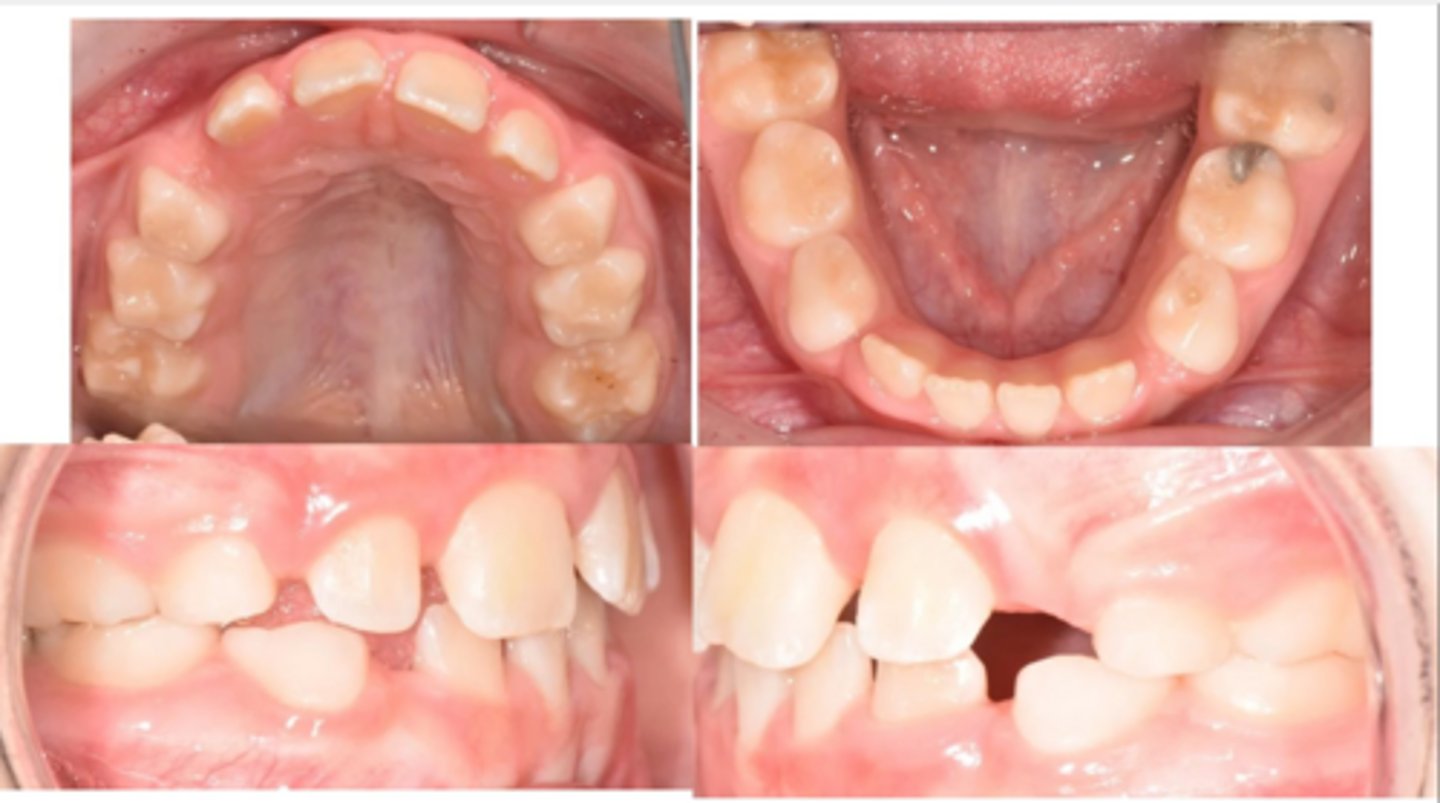

Class II, Subdivision Right

(On the left, she is Class I. On the right, she is Class II. "Class II, Subdivision Right" describes this.)

What type of malocclusion does this patient have?

Premature loss of a molar, which might have caused the shift on just the one side

What might have caused her malocclusion?